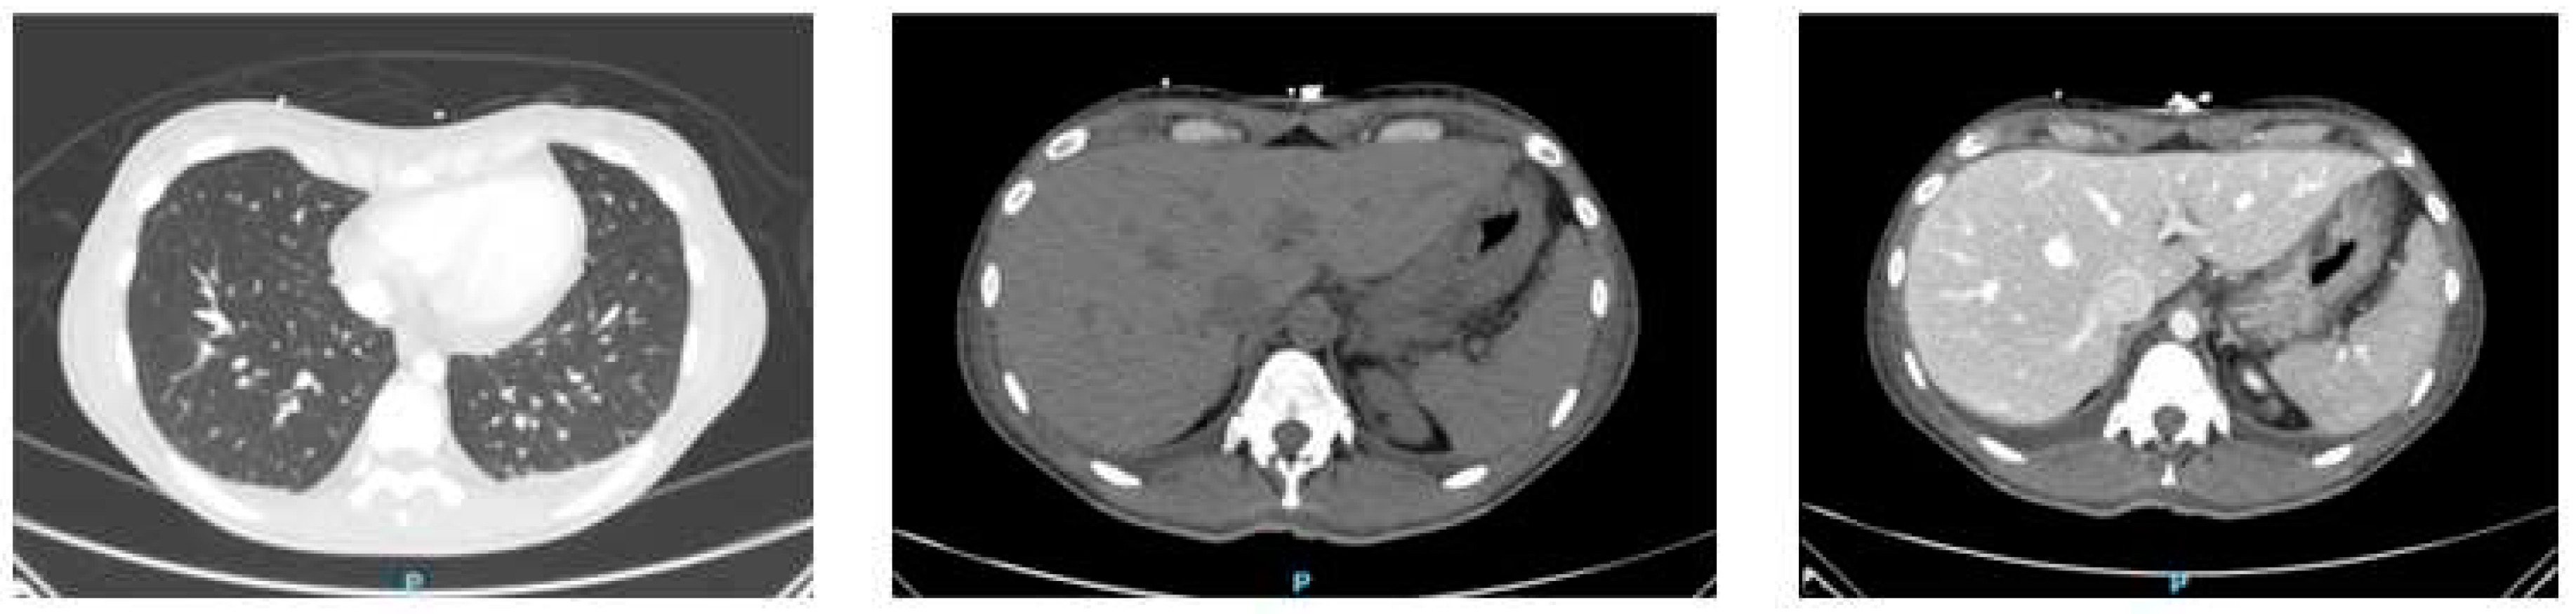

| Cardiac and pulmonary disease [20,21] | Cardiac (non-ischemic) involvements including arrhythmias and pericarditis have been described, as well as pulmonary infiltrates and pleural effusions, which together do not represent a significant proportion of patients, but which should be considered possible and should not confuse the physician in the differential diagnosis. |